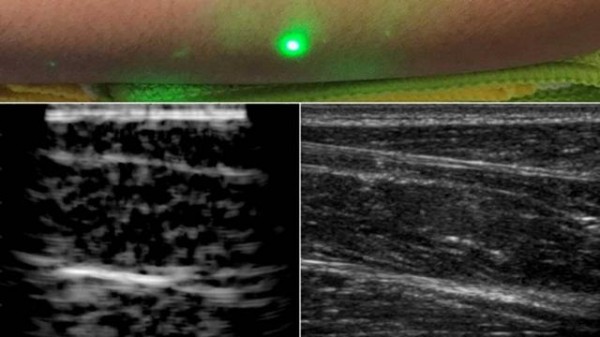

麻省理工學(xué)院研發(fā)無(wú)接觸的激光超聲儀 可以遠(yuǎn)距離產(chǎn)生超聲波圖像

麻省理工學(xué)院設(shè)計(jì)了一種新方法,并使用激光超聲產(chǎn)生了第一批圖像。這項(xiàng)新技術(shù)不需要與身體接觸即可看到患者體內(nèi)。該技術(shù)使用對(duì)眼睛和皮膚安全的激光系統(tǒng)。系統(tǒng)中的一個(gè)激光可以遠(yuǎn)程產(chǎn)生聲波,通過(guò)身體反彈。第二個(gè)激光遠(yuǎn)程探測(cè)反射波,這些反射波被轉(zhuǎn)換成與傳統(tǒng)超聲波相似的圖像。

在測(cè)試中,研究人員用半米外聚焦在志愿者身上的遠(yuǎn)程激光,掃描了幾位志愿者的前臂,并能夠觀察到皮膚以下6厘米深的組織特征,例如肌肉,脂肪和骨骼。這些圖像可與傳統(tǒng)超聲相媲美。

研究小組使用1550nm激光,這種波長(zhǎng)被水高度吸收,對(duì)眼睛和皮膚都是安全的。激光產(chǎn)生清晰可見(jiàn)的脂肪,肌肉和組織邊界的圖像。該團(tuán)隊(duì)計(jì)劃改進(jìn)該技術(shù),并對(duì)其進(jìn)行完善以解決功能上的缺陷。他們還希望提高激光的探測(cè)能力。在未來(lái),他們希望改進(jìn)現(xiàn)有設(shè)備,成為便攜式設(shè)備。